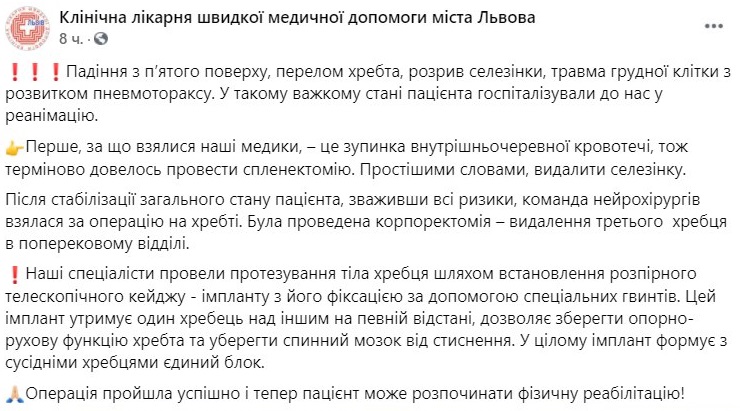

Львовские хирурги провели сразу несколько операций мужчине, который выпал с пятого этажа. В результате он сломал позвоночник, разорвал селезенку и у него начинался пневмоторакс.

"В таком тяжелом состоянии пациента госпитализировали к нам в реанимацию. Первое, за что взялись наши медики - остановка внутрибрюшного кровотечения, поэтому срочно пришлось провести спленэктомию. Простыми словами, удалить селезенку", - указано в сообщении.

Сразу после этого пациенту провели операцию на позвоночнике, закрепив позвонки на безопасном расстоянии для реабилитации в таком положении, чтобы они не раздавили костный мозг.

"Наши специалисты провели протезирование тела позвонка путем установления распорного телескопического кейджа - импланта с его фиксацией с помощью специальных винтов. Этот винт удерживает один позвонок над другим на определенном расстоянии, позволяет сохранить опорно-двигательную функцию позвоночника и уберечь спинной мозг от сжатия", - добавили медики.

Операция была проведена успешно, сейчас жизни пострадавшего ничего не угрожает. Вскоре он сможет начать процесс реабилитации.